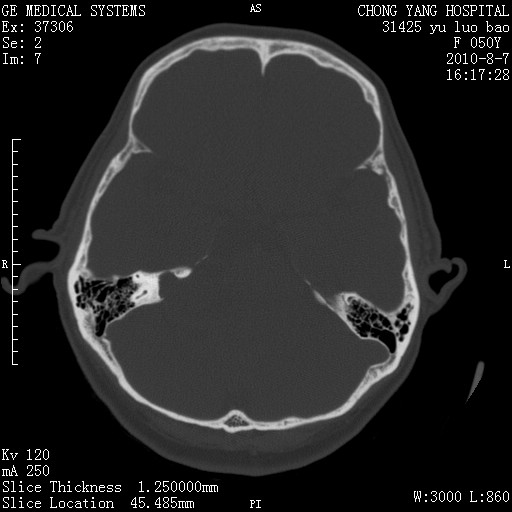

标题: CT28285:听力下降一年,头昏。

右侧桥小脑角去等密度占位,右侧内听道扩大、骨质吸收,考虑:右侧听神经瘤,建议增强检查。

右侧内听道扩大、骨质吸收,中脑受压左移,考虑:右侧听神经瘤,建议增强检查。支持!

骨窗示右侧内听道扩大,考虑右侧听神经瘤。

右侧桥小脑角区等密度占位,内耳道扩大,听神经瘤